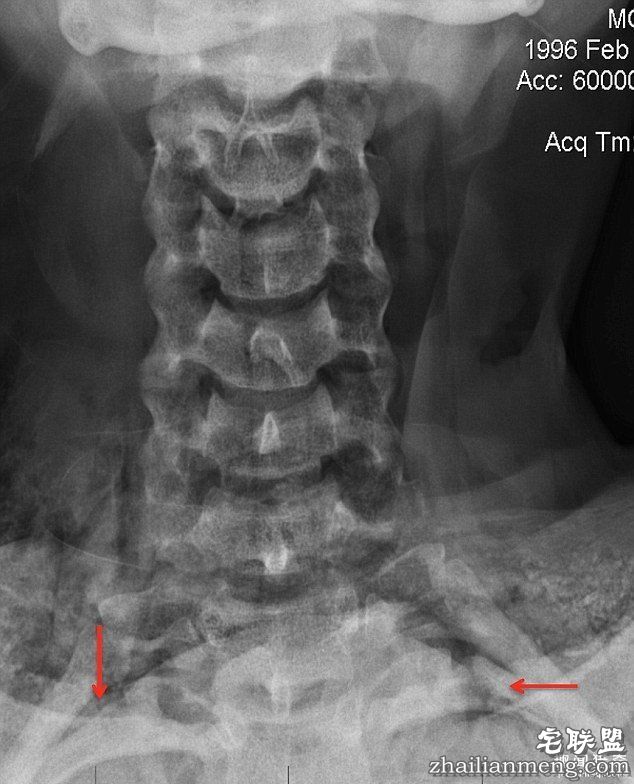

除了鉴识笔迹,荷莉家人还请了私家侦探调查此案,结果发现当时验尸的法医疑似并非持有证照的医生。同时让家人不解的是,X光照显示荷莉的锁骨断裂,手还被卡在她用来吊死自己的电线上,而且綑绑方式极度不顺手,完全不符合上吊死的状况,怀疑法医有所隐瞒。